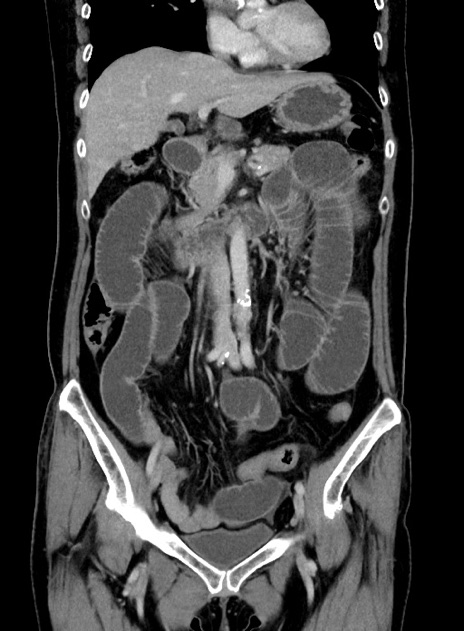

横断像

【症例】 60歳代女性

【主訴】むかつき、みぞおちの痛み

【現病歴】3日前よりむかつきがあり、食事がとれない。

【既往歴】糖尿病

【身体所見】発熱なし、心窩部圧痛軽度あるも、腹膜刺激症状なし。

【データ】WBC 7400、CRP 1.92